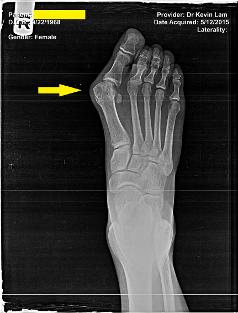

Dr. Kevin Lam Modified the technique to be done in the office and to allow for the quickest healing without any complications. No post operative infection related to this bunionectomy to date due to surgical technique and procedures.

No scar bunionectomy after 4 wks, she is ready for the other foot. Now the left was the bad foot. no bone removed, one stitch. Walk on your heels the first day out of surgery, no cast or crutches, virtually no pain. We do traditional bunionectomies as well as the minimally invasive version as pioneers in this type of surgery. Can understand all types of bunionectomies, surgeons not familiar w the scarless bunionectomy, just don't understand the post op recovery or the stabilization required. Luckily for patients the medical equipment industry has been education more and more surgeons to adopt this. We are the pioneers that others learn from.

Below shows a traditional bunionectomy.

Below shows the new technique immediately post op! Typically surgeons would not show you that due to long incisions and a swollen foot.